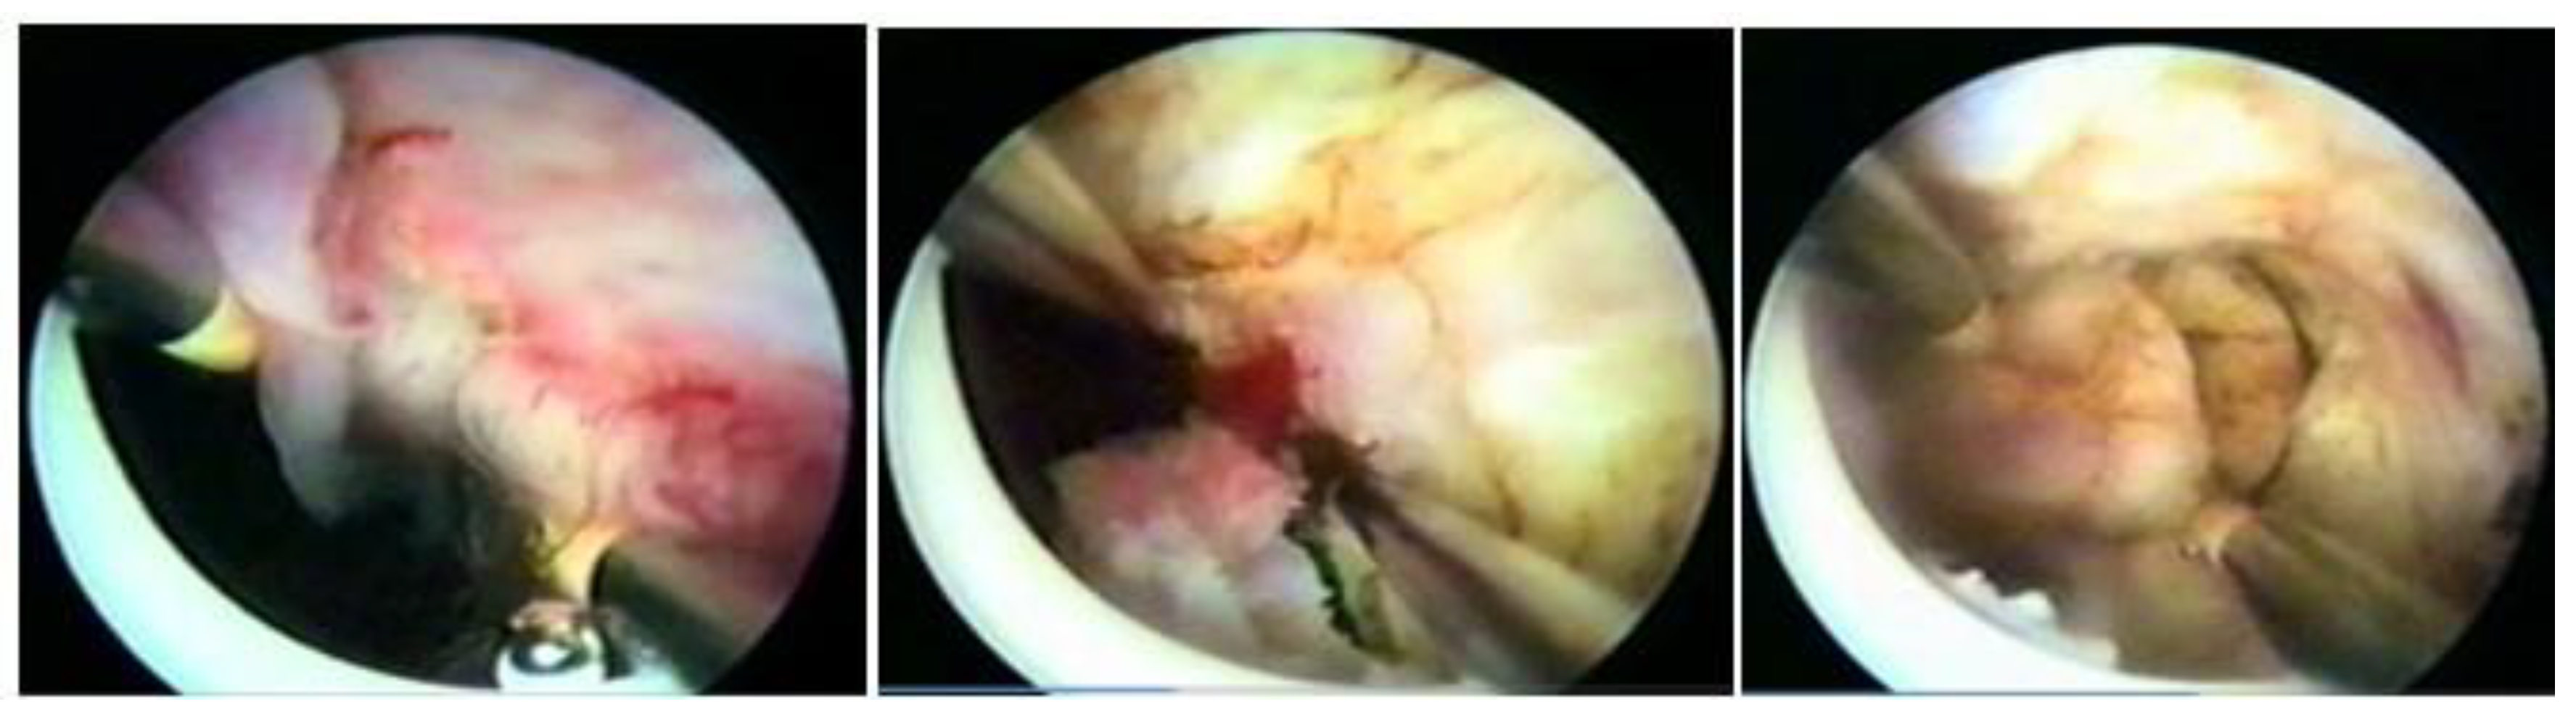

Mazzon’s technique was described in 1995 and is based on the resection of the submucosal component of the myoma using a resectoscope with a semicircle loop, with mono or bipolar energy, until reaching the intramural portion of the myoma. Upon reaching the pseudocapsule, the loop is changed to a more rigid one, which is not energized (cold loop), so that the myoma is mechanically mobilized until its enucleation. Then, a loop with energy returns to fragment and remove the myoma, which was left free in the uterine cavity. It has the advantage of approaching the myometrium without current, with lower risk of perforation and lower risk if perforation happens (thermal injury to other organs), with less thermal damage to the myometrium, less bleeding, and less intravasation [34] (Figure 13).

3.9. Mobilization and Enucleation Technique Using the Pseudocapsule—Lasmar

The technique published by Lasmar in 2002 has the name of “direct mobilization of the myoma”. It consists of incising the endometrium around the submucosal myoma using the resectoscope with the Collins loop until reaching the pseudocapsule, releasing the existing fibrous beams. Once the pseudocapsule is identified, with the same instrument, a movement similar to that performed in laparotomic and laparoscopic myomectomy is performed, separating the myoma from the myometrium in its entirety, causing it to slide into the myometrium.

As there is no traction, as in abdominal surgery, the base of the fibroid is released, starting at the lateral edges, entering with the Collins loop in the cervix–fundus direction without energy at the same time as slight mobilizations in the fibroid are made with the resectoscope assembly. The Collins loop is kept moving from the lateral to the central part of the myoma, parallel to the nodule and moving it with the hysteroscope, leading the myoma to progressively migrate to the uterine cavity until its complete release from the uterine wall. This is facilitated by the decompression of the myometrium, which, compressed by the growth of the nodule, progressively returns to its normal position by releasing the pseudocapsule, causing the intramural lesion to become intracavitary. This technique, like all those that perform myoma enucleation, has the same advantages: lower risk of perforation and risks associated with perforation (thermal injury to other organs), less thermal damage to the myometrium, and less bleeding and intravasation [35].

With the myoma totally in the cavity or almost totally, the nodule is sliced, using the Collins loop, in the longitudinal direction to remove it in large fragments, improving efficiency (Figure 14).

Figure 13. Mazzon technique with “cold loop”.

Figure 14. OR hysteroscopic myomectomy, with Collins electrode, enucleation, and preserving pseudocapsule.